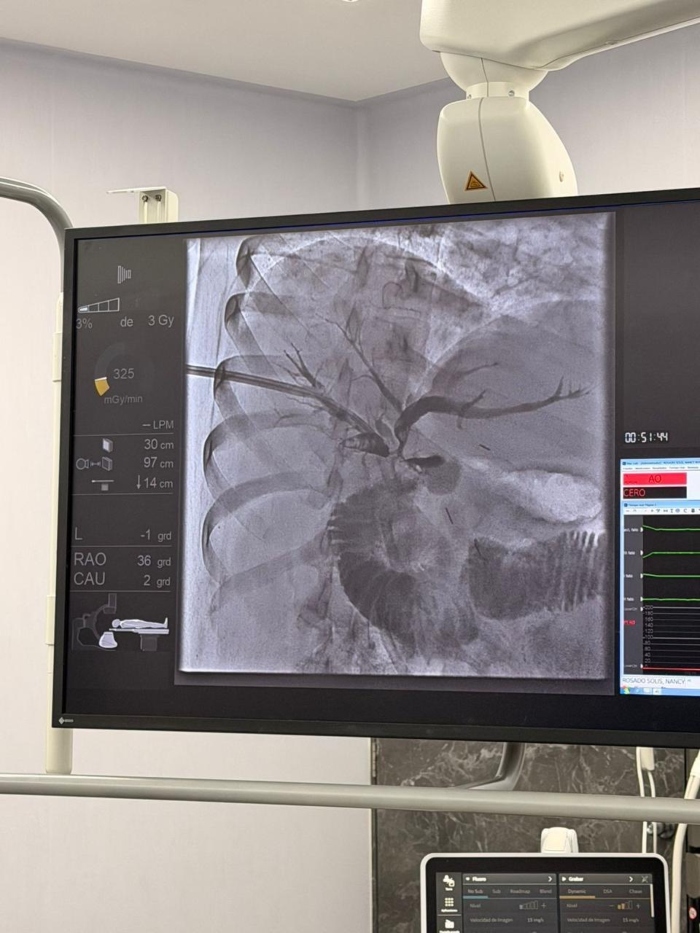

La colangioscopía percutánea es una alternativa altamente especializada que se indica en aquellos casos en los que el acceso endoscópico convencional no es posible, ya sea por modificaciones anatómicas secundarias a cirugías previas o por la imposibilidad para canular el conducto biliar por vía endoscópica, como ocurrió en ambos pacientes atendidos en esta ocasión. Este abordaje permite el acceso directo al sistema biliar de manera mínimamente invasiva, con importantes beneficios diagnósticos y terapéuticos.

La primera intervención se le realizó a una mujer de 32 años, con antecedente de cirugía biliar y litiasis en los conductos biliares intrahepáticos —presencia de cálculos en las vías biliares dentro del hígado—, misma que fue resuelta mediante esta técnica y el uso de litotricia electrohidráulica —método que utiliza ondas de choque para disolver cálculos renales y biliares—, a fin de reducir riesgos y evitar procedimientos quirúrgicos mayores.

El segundo caso fue un hombre de 48 años con diagnóstico de estenosis biliar distal —estrechamiento del conducto biliar común— de origen indeterminado, cuyos estudios de imagen convencionales no permitían establecer con claridad la causa. A través de la colangioscopía se logró la visualización del conducto, así como la toma de biopsias dirigidas, lo que representó un avance significativo para el diagnóstico preciso y el tratamiento oportuno.